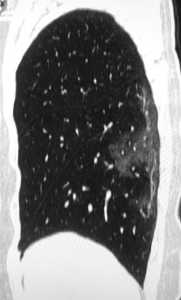

Άλλες σαρώσεις μιας 54χρονης γυναίκας που προσβλήθηκε από τον κορονοϊό μετά από ταξίδι στο Γουχάν, δείχνουν επίσης την ίδια μερική πλήρωση των αεραγωγών.

Η γυναίκα διαγνώστηκε με σοβαρή πνευμονία που προκλήθηκε από τον ιό μετά από πυρετού, βήχα, κόπωσης και θωρακικής συμφόρησης.

Είχε τα συμπτώματα για μια εβδομάδα και της δόθηκε οξυγόνο και αντιβιοτικά.